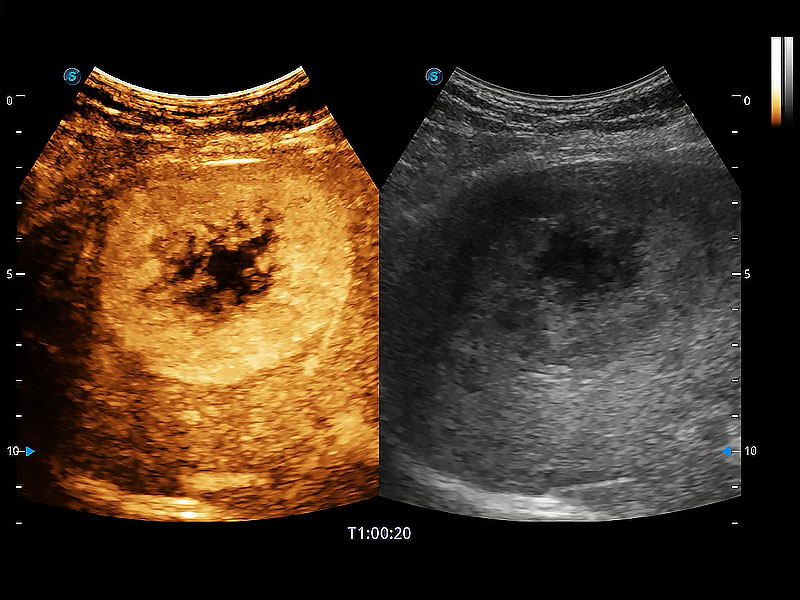

• 全面的造影成像

非线性融合造影成像充分利用谐波和基波信号,为难以观察的血流进行增强显像。可用于线阵、凸阵、微凸阵、相控阵探头。

(犬)肝脏

(猫)胆囊